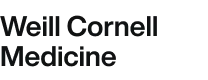

FORMsightAI optimizes AAV vector genomes and large/complex payloads, improving integrity, reducing truncations, and enabling tunable expression.

Demonstrated up to 5x improvements in genome integrity and 4.4x yield gains, directly lowering COGS and supporting efficient clinical translation.

Genome Integrity Analysis

A clear, structured approach for characterizing genetic medicine

Drug Product Insights

Gain a clear view of what’s encapsidated— distribution of full vs. partial genomes and contaminated species.

Our model aligns with your goals, optimizing across multiple objectives while managing tradeoffs like increasing expression vs. minimizing truncations.